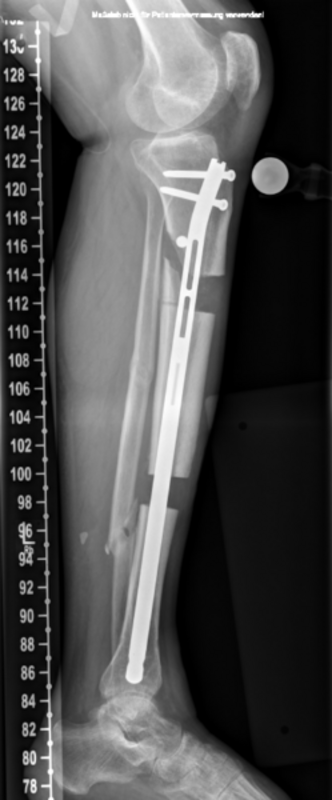

Kurze Vorgeschichte: Herr S, ein 67-jähriger Patient, erhielt 2011 (Abbildung 1) bei ausgeprägter Gonarthrose eine primäre KTEP rechtsseitig. Im weiteren Verlauf zog er sich 2017 eine periprothetische Tibiafraktur zu, die mit einem Knieendoprothesenwechsel auf ein achsgeführtes Implantat (Abbildung 2) und Schaftverlängerung der Tibia im September 2017 ex domo therapiert wurde. Im Verlauf zeigten sich eine anhaltende Sekretion und eine partielle Nekrose am unteren Wundpol.

Eine Röntgendiagnostik des rechten Kniegelenkes in 2 Ebenen wurde eingeleitet. Hierbei zeigte sich eine stabil einsitzende Revisionsprothese ohne aktuelle Lockerungszeichen.

Im weiteren Verlauf zeigten sich die Weichteile des rechten Unterschenkels zunehmend mazeriert und belegt. Zudem sei der Patient erneut gestürzt. Eine erneut durchgeführte Röntgendiagnostik zeigte erneut eine periprothetische Tibiafraktur (Abbildung 3) bei einliegender achsgeführter KTP mit langem tibialem Stem und bekanntem periprothetischem Infekt mit Candida parapsilosis. Wir haben die Befunde ausführlich mit dem Patienten besprochen und in Zusammenschau der Befunde schließlich die Indikation zur Oberschenkelamputation gestellt.